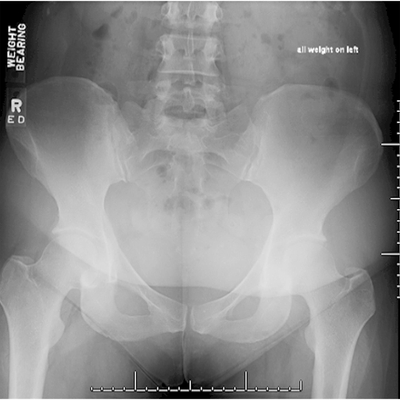

Click on an image below to view more info.